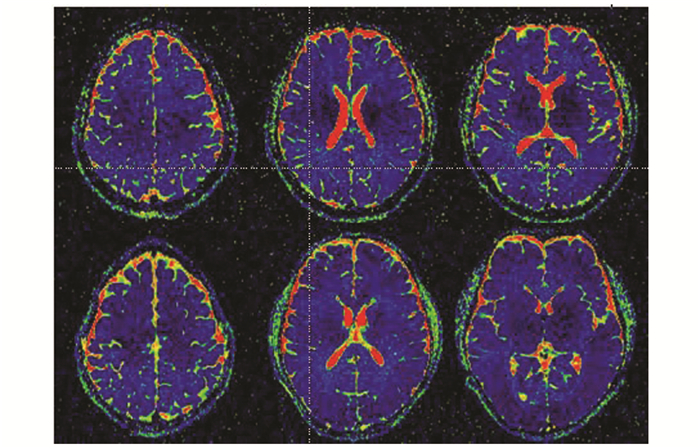

2.2 IVIM参数值比较与HIV-组比较,HIV+组尾状核和额叶白质D*值显著降低,尾状核为(4.49±1.04)10-3mm2/s比(5.32±0.47)10-3mm2/s,P=0.005;额叶白质为(4.68±0.39)10-3mm2/s比(5.27±0.68)10-3mm2/s,P=0.003;而两组尾状核和额叶白质D值差异无统计学意义,尾状核(0.77±0.05)10-3mm2/s比(0.75±0.03)10-3mm2/s,P=0.121;额叶白质为(0.82±0.04)10-3mm2/s比(0.81±0.04)10-3mm2/s,P=0.623;两组尾状核和额叶白质f值差异亦无统计学意义,尾状核(5.30±0.81)%比(5.67±0.54)%,P=0.115;额叶白质(5.41±1.46)%比(5.55±0.42)%,P=0.722](表 2,表 3,图 1-3)。

图 2 D*值伪彩图 上排HIV+组,下排HIV-组;P<0.05 |

图 3 f值伪彩图 上排HIV+组,下排HIV-组;P>0.05 |